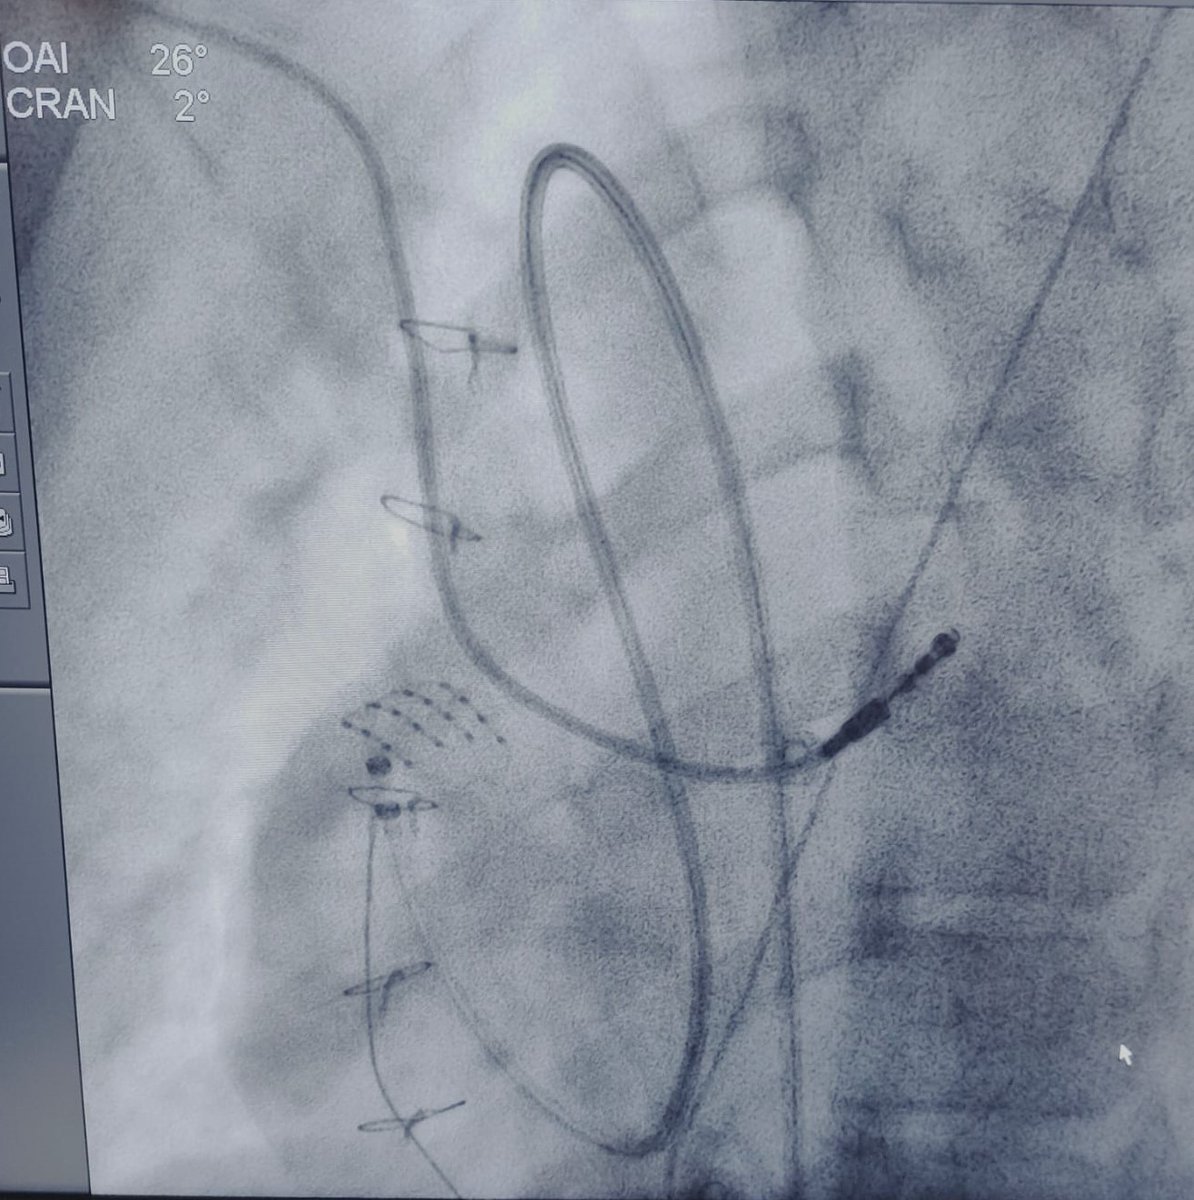

Safety and efficacy of intracardiac echocardiography in #AtrialFibrillation ablation: A meta-analysis